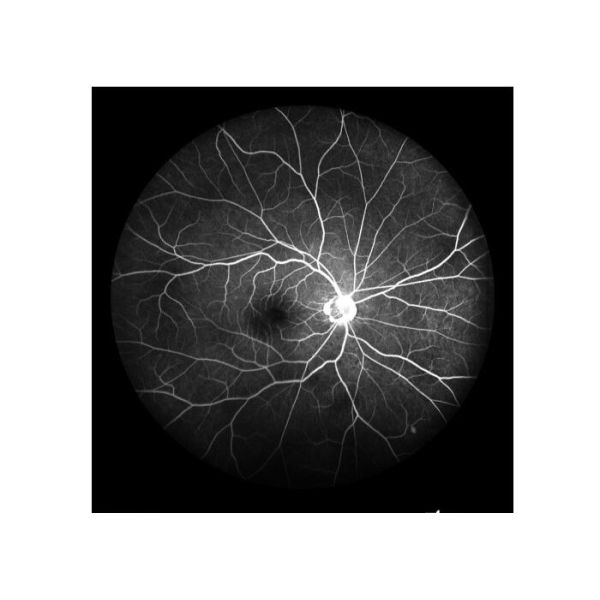

Angiografía de la fluoresceína del fondo (FFA): Cambio circulatorio retiniano |

1) “Estándar de oro” para juzgar enfermedad de la retina 2) Para reflejar la patología fisiológica de los vasos sanguíneos retinianos a los capilares 3) Para examinar completo las enfermedades desapercibidas en el examen normal del fondo |